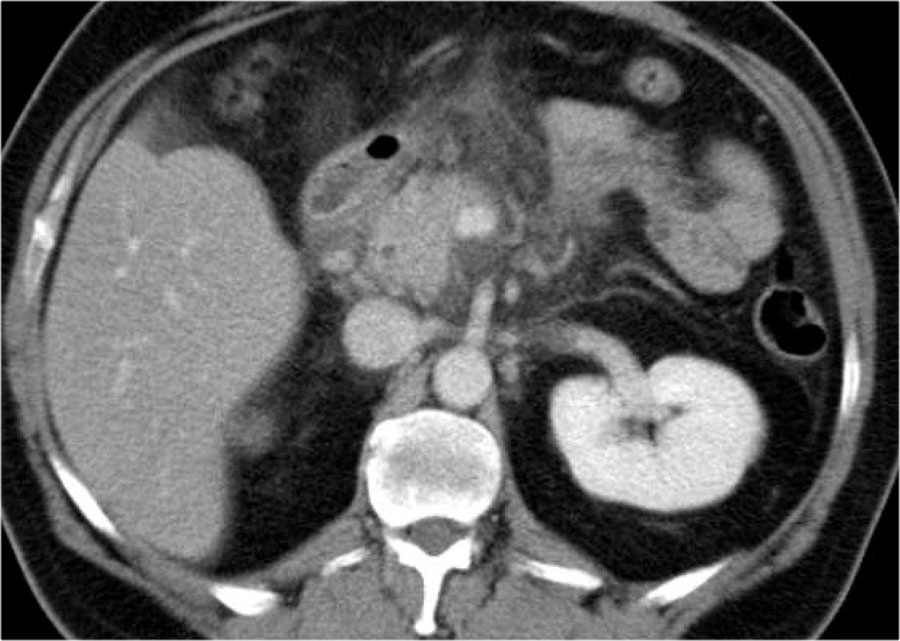

Các hình ảnh cho thấy tụy ngấm thuốc bình thường vào ngày thứ 1.

Khi tình trạng bệnh nhân xấu đi, CT lần hai được thực hiện vào ngày thứ 3.

Lưu ý phần lớn thân và đuôi tụy không còn ngấm thuốc, gợi ý viêm tụy hoại tử (các mũi tên).

CT lần đầu đã đánh giá thấp mức độ nặng của viêm tụy.

Bệnh nhân này tử vong vào ngày thứ 5 do hội chứng đáp ứng viêm hệ thống (SIRS) nặng và suy đa tạng.